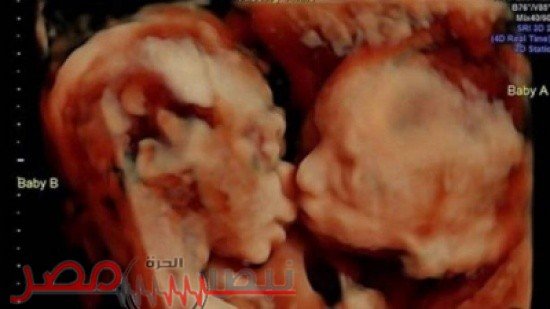

صورة اليوم : قبلة توأم داخل أحشاء الوالدة تُشعل مواقع التواصل الاجتماعي!!

وفي التفاصيل، زارت غاريسا غيل الحامل بتوأم في الأسبوع الـ 25 عيادة الطبيب في بنسلفانيا مع زوجها راندي الأسبوع الماضي.

ولكنهما تفاجآ وفرحا عندما شاهدا طفلتيهما في صورة الموجات فوق الصوتية وهما تتبادلان قبلة.

وتعليقاً على ما حصل علّقت الأمّ غاريسا لـ Fox 29 بالقول إنّ فترة الحمل هي الأجمل خصوصاً عندما يتعلّق الأمر برؤية صور الموجات فوق الصوتية.

يُشار إلى أنّ الثنائي قرر تسمية التوأم إيزابيلا وكالي. واللافت أنّ غاريسا نشرت الصورة على فيسبوك علّقت عليها بالقول :”إيزابيلا تقبل كالي على خدّها.”

الجدير بالذكر، أنّ هذه العيادات تعطي الموجات فوق الصوتية بـ 3 تقنيات الـ 3D، 4D والـ HD.